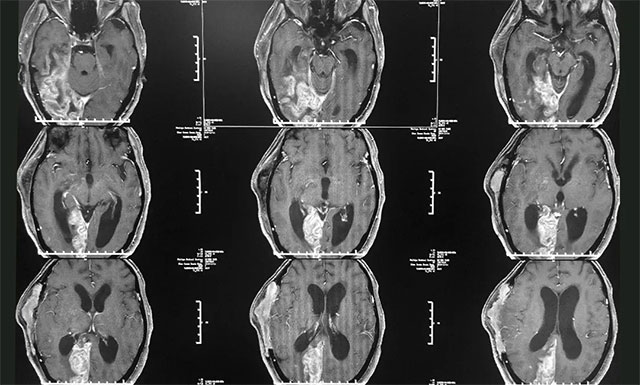

患者葛女士顱內(nèi)重度感染,情況不容樂(lè)觀,對(duì)此吳治群博士介紹說(shuō):“患者因其之前腦膿腫比較嚴(yán)重,術(shù)后又出現(xiàn)了一系列并發(fā)癥,顱內(nèi)嚴(yán)重感染,伴顱內(nèi)高壓,腦積水也非常嚴(yán)重;來(lái)院時(shí)患者就陷入了深度昏迷,當(dāng)時(shí)她的拉斯哥昏迷評(píng)分(GCS)僅有6分(GCS評(píng)分最高為15分,分?jǐn)?shù)越低則意識(shí)障礙越嚴(yán)重);又因之前行去骨瓣減壓術(shù),患者右側(cè)顳頂骨大塊缺損,腦組織凹陷,腦室受壓變窄,情況危急,并收治于6B神經(jīng)外科監(jiān)護(hù)病房”。

▲ 患者顱內(nèi)感染嚴(yán)重,情況非常危急

完善各項(xiàng)檢查后,潘主任和吳主任針對(duì)其病情進(jìn)行了會(huì)診,一致認(rèn)為患者目前顱內(nèi)感染嚴(yán)重,并引發(fā)了腦積水,需要及時(shí)手術(shù),否則會(huì)破壞大腦功能,嚴(yán)重時(shí)則可能形成腦疝,甚至昏迷及死亡。隨后,潘主任醫(yī)生團(tuán)隊(duì)制定了完善周密的治療方案。